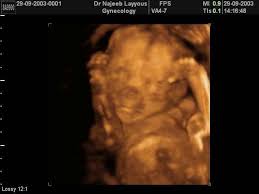

الحمل في الشهر السادس الدكتور نجيب ليوس

أعراض الحمل في الشهر السادس نمو الجنين من الأسبوع 23 إلى 27 طبيب دوت كوم

مراحل النمو و التطورات التي تطرأ على الأم و الجنين في الشهر السادس من الحمل كبسولة